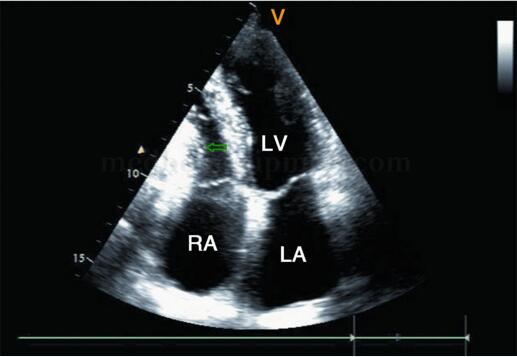

图2‐1‐230 缩窄性心包炎 A﹒显示心包回声增强,双心房增大,双心室相对较小;B﹒显示室间隔摆动,舒张期突向左室侧;C﹒房间隔舒张期突向左房侧;D﹒下腔静脉显著扩张

超声描述 左房增大,右房内径正常上限,左、右心室相对较小。室间隔呈矛盾运动,舒张期明显向左室一侧膨隆。房间隔向左房一侧轻度突出。升主动脉及主肺动脉内径不宽。左室壁厚度正常,静息状态下未见节段性室壁运动异常,左室整体收缩功能正常,舒张活动轻度受限。各瓣膜形态结构正常,收缩期三尖瓣见极少量反流,余瓣膜启闭正常,各瓣膜血流频谱随呼吸运动流速变化异常。心包腔内未见明显液性暗区。脏层心包增厚,最厚处约6mm,脏壁层粘连。下腔静脉内径增宽,塌陷指数减低,静脉内血流缓慢。腹腔内可见大量游离液体。

超声诊断 脏层心包增厚;左、右心房相对增大;下腔静脉增宽,塌陷指数减低;大量腹腔积液;结合临床考虑缩窄性心包炎。

2﹒二维超声心动图 提示缩窄性心包炎的征象包括心包不同程度增厚,回声增强,尤以房室瓣环处为著,见图2‐1‐232;部分患者的心包可出现钙化,见图2‐1‐233,钙化的心包后方可出现明显的声影;四腔心切面可显示双心房增大、双心室相对较小,见图2‐1‐232;剑下四腔心切面可显示心包膜增厚、回声增强的程度,心室收缩及舒张受限;大动脉短轴及左心室长轴切面均可显示左心房增大。部分患者可出现不同程度心包积液(图2‐1‐234),心包腔内可见絮状物回声。由于心房压力增高,上下腔静脉、肝静脉扩张,且扩张的下腔静脉、肝静脉内径随呼吸变化不明显。

图2‐1‐232 缩窄性心包炎,右室侧壁及右房室沟心包回声增强